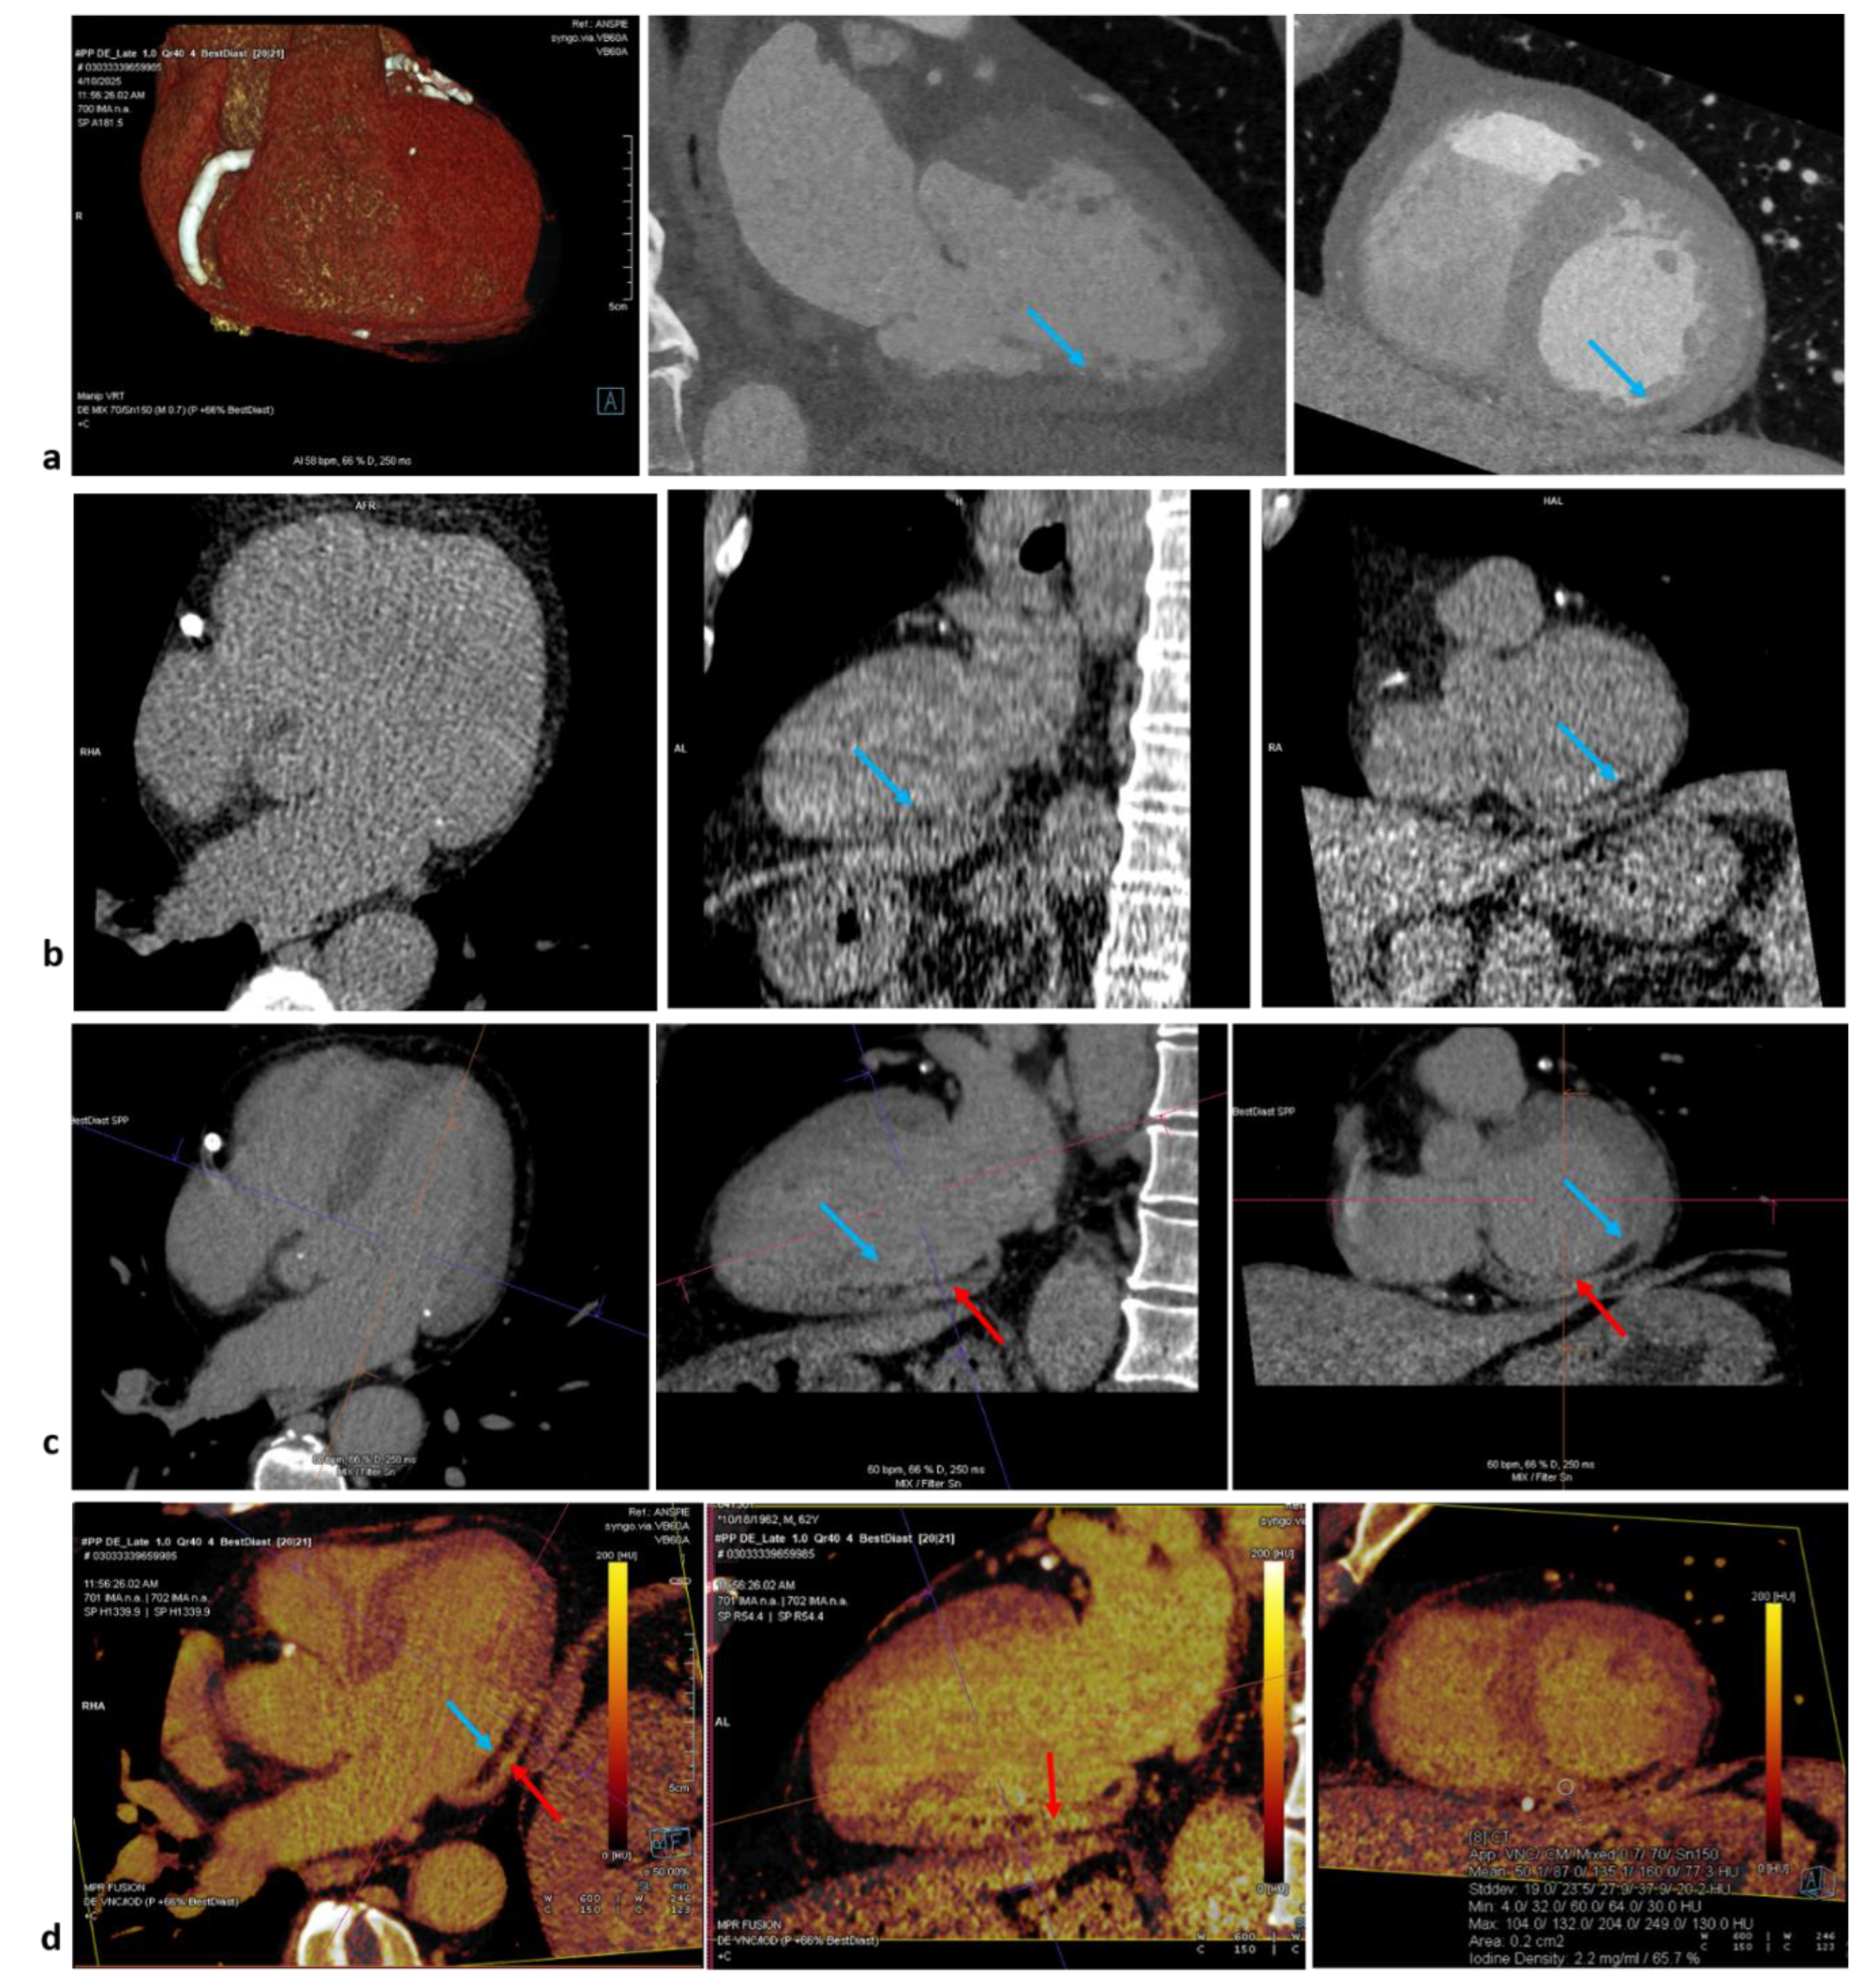

Since both gadolinium and iodinated contrast media share similar pharmacokinetic properties [10], the approach of late gadolinium enhancement can be translated also to cardiac CT. An issue remains the lower contrast-to-noise (CNR) in comparison to CMR. To resolve, a lower voltage dose could be an option for single energy but suboptimal for lower spatial and temporal resolution. Dual–energy computed tomography (DECT) instead allow the reconstruction of monoenergetic images at lower energy levels and with direct quantification of iodine concentration through two-material decomposition technique, obtaining a iodine map. Late enhancement can be detected as hyperintensity of signal on both energy methods and as higher iodine concentration at dual-energy method (Figure 1).

Figure 1. Late Iodine enhancement polar map, dual-energy (Somatom Force, Siemens Healthcare). This case show a case of transmural Late Iodine Enhancement LIE (red arrowst in mid-to-basal portion of inferior and infero-lateral walls (panel d), with inferior fat metaplasia (blue arrows), in patient with ischemic heart disease (previous ST-elevation myocardial infarction and subsequent stenting on the tree vessels). Panel a shows 3D- heart view and angio-CT appearance of fat metaplasia, as confirmed in basal scans (panel b). Panel c shows LIE in the monoenergetic map (40 kV), where LIE can be better visualized as hyperintensity of signal, surrounding fat metaplasia. Panel d shows LIE in the polar map calculating the quantity of Iodine density in percentage (ROI in short axis view, at right), for the quantitative evaluation by the Heart PBV toll (Siemens).

Figure 4. CT application in study of valve degenerations. Panel a shows biological prosthesis degeneration (Trifecta 23, implanted in 2015), with thickening of the cusps in particular in the periannular regions, as suspected at echocardiography study which revealed severe aortic valve regurgitation. The patients, symptomatic for dyspnoea, was treated with TAVI valve-in-valve replacement, after CT anatomical pre-procedural study. Panel b shows asymptomatic HALT in a TAVI patient (implanted in 2021, CT in 2023) with thickening of all the leaflet (mean 5 mm) partially viewable at venous scans and tissue with HU 100-to-125 as for mainly fibrotic tissue with suspected superimposed thrombus, in agreement with high echocardiographics gradients with paravalvular leak. The patient was treated with warfarin, with efficacy reduction of gradients and normal follow-up at 2025.